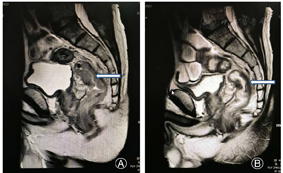

患者,男性,62岁。因"大便性状改变6个月余"于2017年2月9日入院。患者半年来交替出现便血、便秘、腹泻,加重伴肛门坠胀、疼痛、里急后重感,患者及家属未予以重视,未曾到当地医院行相关检查及治疗,此后上述症状反复发作,于3个月前症状加重。患者既往无高血压、冠心病、糖尿病等慢性病史。查体:腹部无明显阳性体征,直肠指诊距肛门口5 cm处可触及肿物下缘,退出指套染血。行电子结肠镜检查时发现距直肠下段处可见菜花样隆起性肿物,占据整个肠腔,致管腔阻塞,结肠镜未能通过,活检结果提示中分化管状腺癌,异型腺体弥漫性分布,排列呈乳头状及筛孔,核形不规则,染色质颗粒状,核仁明显,分裂相易见,细胞质量中等,粉染,胞界不清。血常规提示:白细胞8.97×109/L,血红蛋白163 g/L,血小板283×109/L,癌胚抗原14.29 ng/ml,大便隐血实验阳性,其余实验室检查均在正常范围内。盆腔MRI提示直肠管壁不均匀增厚,肠腔狭窄,病变与周围脂肪间隙不清,考虑直肠癌(T4N1M0)。因肿瘤较大、分期较高,经多学科协作讨论后,术前给予新辅助放化疗,具体方案为计划靶区41.80 Gy/22 f,计划大致肿瘤靶区50.6 Gy/22 f;同步口服卡培他滨1 500 mg(早上)、1 000 mg(晚上)。于本次入院查癌胚抗原4.84 ng/ml,大便隐血实验仍为阳性。心电图、X线胸片、腹部超声未见明显异常。腹部增强CT提示直肠放疗后改变,直肠中段管壁增厚。盆腔MRI提示直肠放疗后改变,较2017年2月9日片比较管壁增厚及管腔狭窄情况明显好转,瘤体显著缩小,淋巴结变化不大(见封四,图1)。术前诊断为:直肠癌,T3N1M0。于2017年2月15日在全身麻醉下行腹腔镜辅助直肠癌行直肠全系膜切除术(Total mesorectal excision, TME)。术后给予营养支持、抗感染、抑酸等治疗,患者于术后3 d恢复通气,后逐步恢复到正常饮食,术后7 d恢复良好出院。术后病理提示:直肠中分化腺癌,大小为1.7 cm×1.6 cm×0.6 cm,侵及壁肌层,脉管、神经未见明确侵犯,两侧切缘(-),肠系膜淋巴结未见癌转移。后续给予FOLFOX方案规律化疗6次,化疗期间患者无恶心、呕吐等化疗相关反应,每次化疗均复查肿瘤标志物及腹部增强CT,也未见肿瘤复发表现。化疗结束后持续随访半年余,实验室检查及影像学检查均未发现复发迹象,期间患者排便、排尿可,大便成形,无腹泻、便细等大便性状改变症状。现患者每半年复查腹部CT、肿瘤标志物、粪常规等。

本例中,术前没有明确发现患者是右位乙状结肠,术后重新阅片,与影像科专家讨论,结合手术中所见,明确发现盆腔CT与MRI中有显示乙状结肠位于患者右下腹(见封四,图3)。本例优势在于该患者行腹腔镜下直肠癌根治术,故腹腔镜探查时即发现乙状结肠位于患者右下腹,随即术者换位于对侧行手术游离,术者腹腔镜技术娴熟程度对于罕见病例手术的成功也有关键作用。TME由Heald等[9]于1982年首次提出,经过近20年的临床实践表明,TME术后直肠癌的术后复发明显减少,患者的5年生存率也明显改善。然而关于TME术中IMA的处理方式,目前绝大多数专家推崇高位结扎,即自腹主动脉发出后的IMA起始处结扎。本例中术中可见肠系膜下动脉转向右侧,并分出相应的左结肠动脉、乙状结肠动脉、直肠上动脉,遂从IMA根部结扎。术后病理示淋巴结检出11枚,均未见癌转移。术后患者未见吻合瘘且排便、排尿均正常。然而并不是所有的右位乙状结肠患者均存在同样的血管分支,例如在Indrajit等[10]研究中发现右位肠系膜下动脉向上发出右结肠动脉,向下分出降结肠动脉及直肠上动脉,因此对于此类右位乙状结肠合并结直肠肿瘤的患者,术中应仔细解剖各血管分支以免错误结扎血管并引起相应肠管的坏死。再者,术前也有必要通过血管造影的方法确定血管走行。此外,因右位降结肠、乙状结肠位置的特殊性,在行直肠肿瘤切除过程中,尽量多游离降结肠及横结肠,避免术后肠管形成折角导致术后肠梗阻。